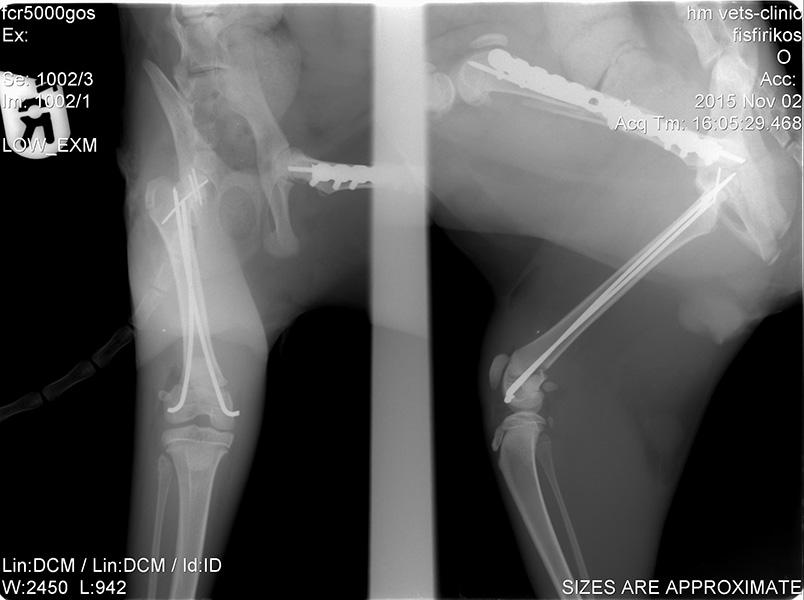

Ορθοπεδική

Ορθοπεδική

Το κτηνιατρείο hm vets αναλαμβάνει ψηφιακή ακτινογραφία, έλεγχο δυσπλασίας ισχίου, ορθοπεδική-νευροχειρουργική, χειρουργική μαλακών μορίων, οφθαλμολογία, εσωτερική παθολογία και εργαστηριακές εξετάσεις (αίματος, βιοχημικές, ανοσολογικές, ορμονολογικες, μοριακές και ιστοπαθολογικές).

Το κτηνιατρείο hm vets αναλαμβάνει ψηφιακή ακτινογραφία, έλεγχο δυσπλασίας ισχίου, ορθοπεδική-νευροχειρουργική, χειρουργική μαλακών μορίων, οφθαλμολογία, εσωτερική παθολογία και εργαστηριακές εξετάσεις (αίματος, βιοχημικές, ανοσολογικές, ορμονολογικες, μοριακές και ιστοπαθολογικές).